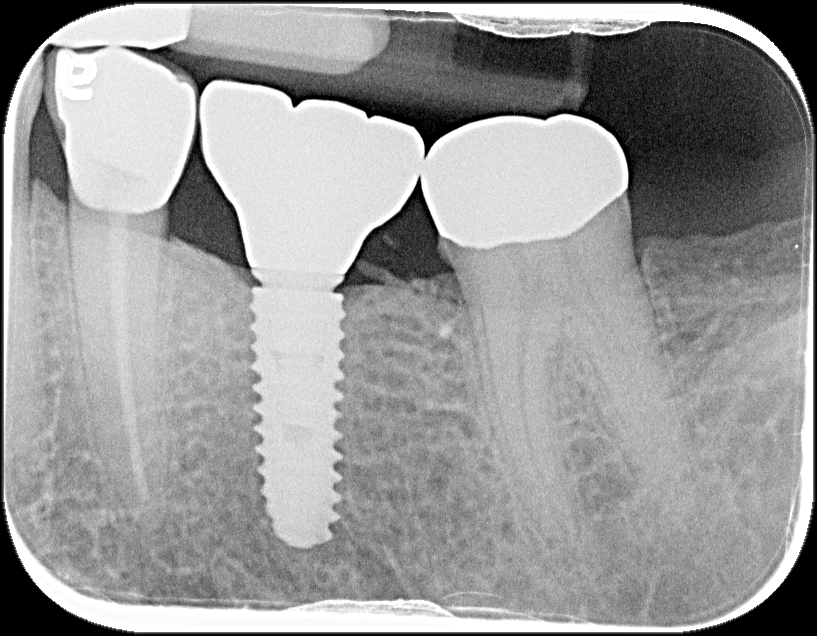

A dental implant is like a tooth root made out of titanium post and is surgically positioned either into the jaw bone or onto the bone, so a replacement tooth or bridge can be fixed to the implant. Dental implants also benefit general oral hygiene because they do not have to be anchored to other teeth, like bridges.

Dental implants are an excellent solution for replacing missing teeth, offering durability, functionality, and a natural appearance. To ensure the success of your implant treatment, our dentists at Carvolth Dentistry conduct a thorough evaluation of your oral health. This includes assessing your oral hygiene, taking necessary X-rays—including advanced 3D X-rays (Cone Beam Computed Tomography)—and examining the condition of your gum tissues and bone density. By carefully planning each step, we ensure optimal implant placement and long-term success.

Dental implants are titanium posts surgically placed into the jawbone to serve as artificial tooth roots. They provide a strong foundation for replacement teeth such as crowns, bridges, or dentures.